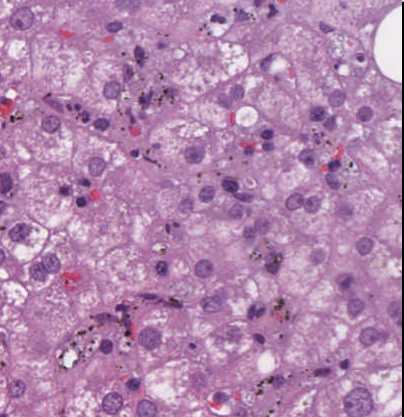

Leberbiopsie mit Nachweis von Plasmodien in den Erythrozyten und Hämozoinpigment in den Kupfferzellen bei bekannter Malaria tropica.

Mikroskopie

Leberbiopsie mit regelrechter Läppchenarchitektur. In den Portalfeldern ein mononukleäres Entzündungsinfiltrat ohne Nachweis einer Bindegewebsfaservermehrung. Die trabekulär angeordneten Hepatozyten mit fedriger Degeneration und Bilirubinostase. In 20% der Hepatozyten finden sich überwiegend großtropfige Neutralfetteinlagerungen. Kein Nachweis von hepatozytären Eisenablagerungen. Die Sinusoide erweitert, mit Mesenchymaktivierung und mit Erythrozyten gefüllt, in welchen Plasmodien nachweisbar sind. Die Kupfferzellen mit kleinklumpigen sog. Hämozoinpigment. Fokal findet sich ein lipophages Granulom.

Eine chronische Schädigung, oder ein zirrhotischer Umbau sind nicht nachweisbar.

In den Sinusoiden lässt sich in CD68 positive Kupfferzellen ausgedehnt Hämozoinpigment (=Malariapigment) nachweisen.

Die sinusoidale Hämozoinspeicherung spricht für eine persistierende Plasmodienreplikation.

Abb. 126: Malariapigment in den Kupffer-Zellen.